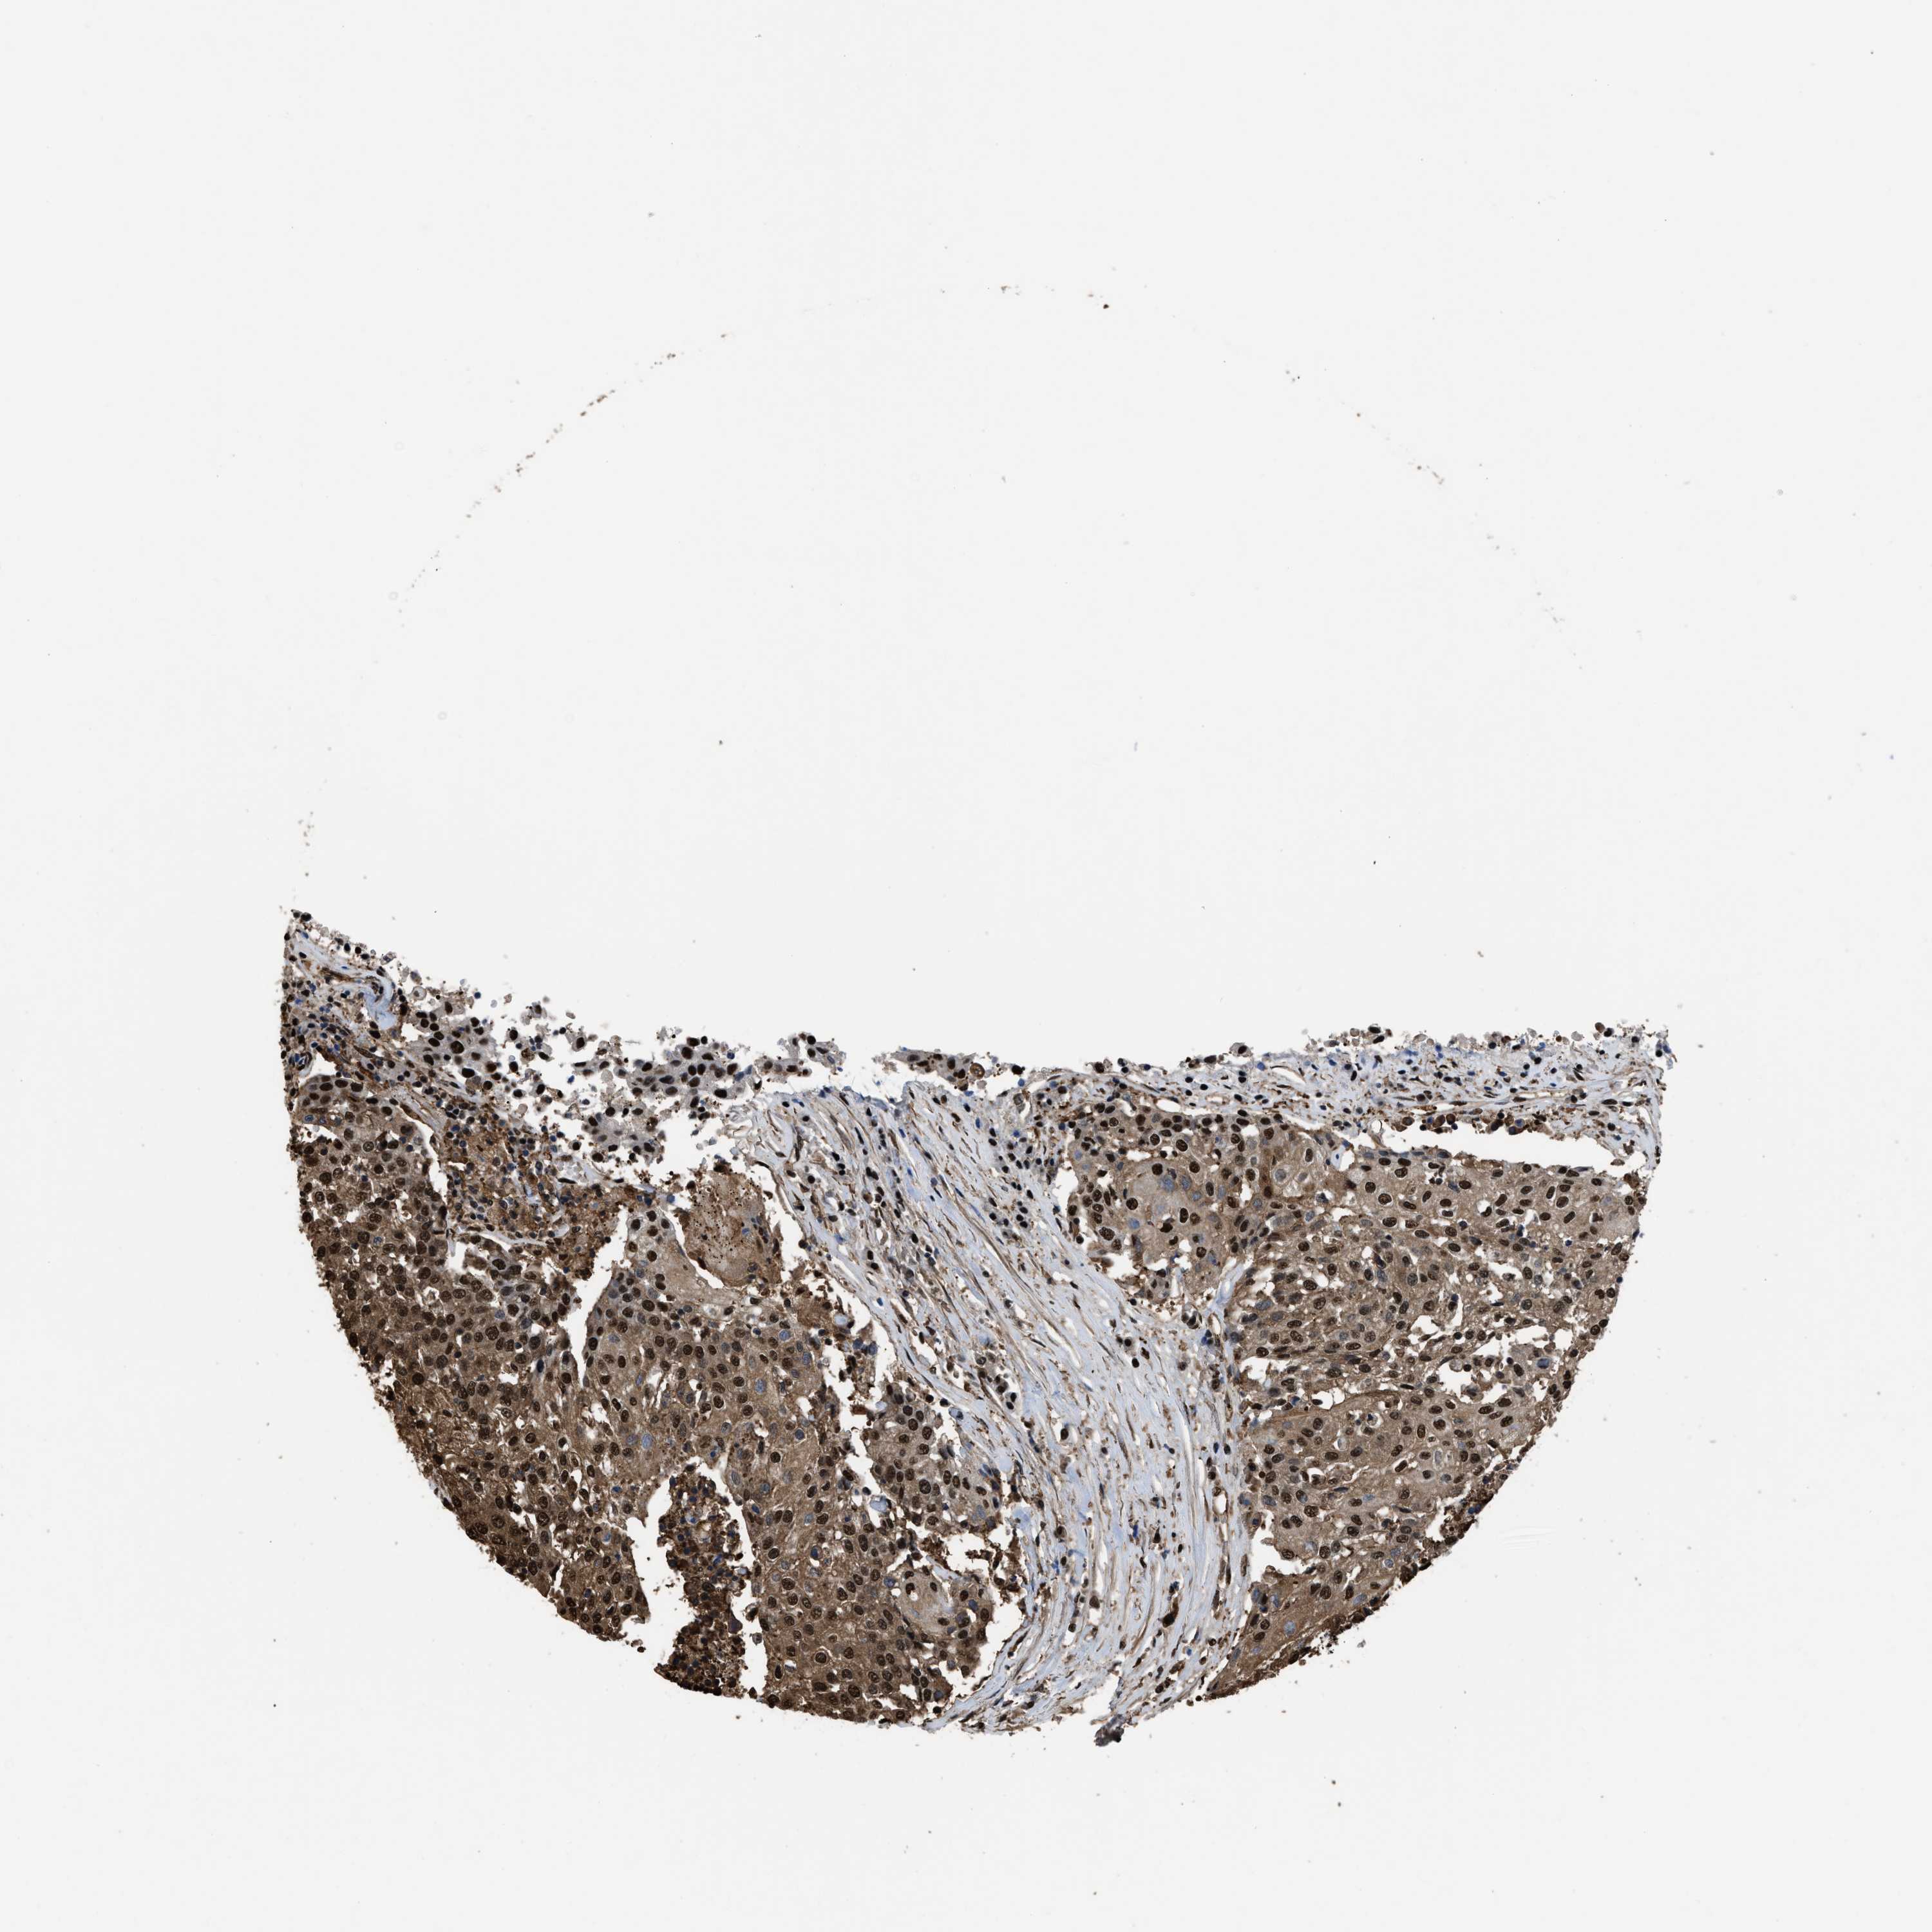

UROTHELIAL CANCER - Protein expressioni

A mouse-over function shows sample information and annotation data. Click on an image to view it in a full screen mode. Samples can be filtered based on level of antibody staining by selecting one or several of the following categories: high, medium, low and not detected. The assay and annotation is described here.

Antibody stainingi

Antibody staining in the annotated cell types in the current human tissue is reported as not detected, low, medium, or high, based on conventional immunohistochemistry profiling in selected tissues. This score is based on the combination of the staining intensity and fraction of stained cells.

Each image is clickable and will lead to virtual microscopy that enables deeper exploration of all samples and also displays staining intensity scores, fraction scores and subcellular localization as well as patient and tissue information for each sample.

Antibody HPA018830

Antibody CAB010149

Staining

High

Medium

Low

Not detected

Intensity

Strong

Moderate

Weak

Negative

Quantity

>75%

75%-25%

<25%

None

Location

Nuclear

Cytoplasmic/membranous

Cytoplasmic/membranous,nuclear

Urothelial carcinoma, Low grade

Urothelial carcinoma, High grade